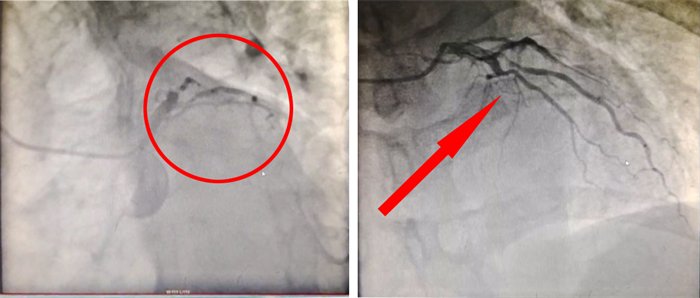

▲患者PCI术前(左)、术后(右)血管情况

11:57分,成功穿刺后,开始造影、定位;

12:16分,导丝通过患者闭塞血管段,血流的重新灌注标志着血管成功开通。